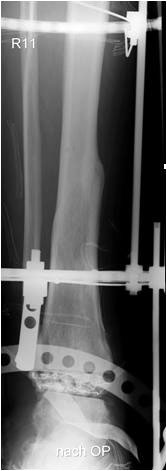

• Primäre oder posttraumatische Arthrose des OSG und USG (Abbildung 1, Abbildung 2).

• Revision einer gescheiterten Fusion des OSG/ USG (Abbildung 3, Abbildung 4).

• Ausgeheilte (!) Osteomyelitiden (Abbildung 7, Abbildung 8, Abbildung 9, Abbildung 10).

• Spezielle Indikationen (Abbildung 11, Abbildung 12).